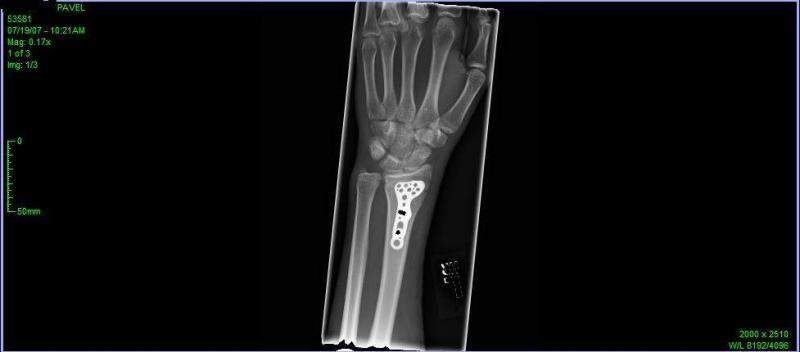

Недавно руку поломал, и чтобы кости вместе скрепить вставили титановую фиговину.

Подвижность кисти уже не такая, но думаю это временно. В классическую позицию трудно ставить.

А пальцы нормально двигаются :)